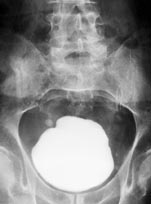

Røntgen oversikt abdomen viste en stor forkalkning i blæreregionen (fig 1). Intravenøs urografi viste forsinket utskilling fra venstre nyre og utvidelse av begge nyrebekkener og urinledere. Serum-kreatinin var normal. Cystoskopi var ikke mulig å gjennomføre, fordi steinen hindret cystoskopet i å passere gjennom en sklerotisk blærehals. Preoperativ miksjonsliste ble ikke ført, og det ble ikke gjort urinstrømsmåling.